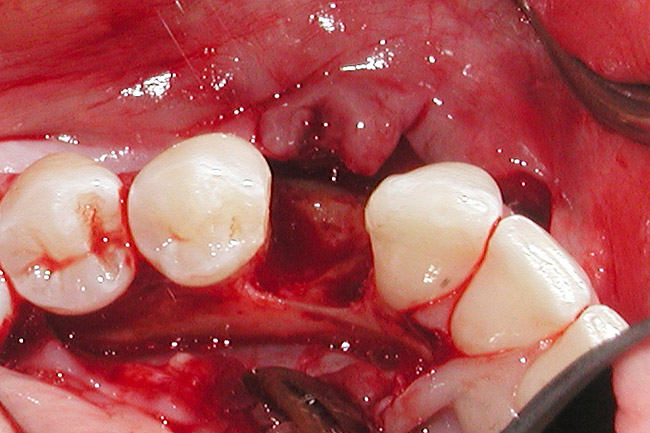

Figure 4  Vertical ridge defect in site No. 22.

Figure 4

Figure 5  Horizontal ridge defect in site No. 22.

Figure 5